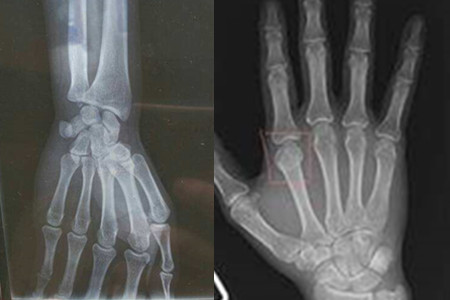

其实日常生活中我们使用右手的概率比左手要多很多,所以右手很容易受伤,无论在哪个年龄层都是一样的,生活中难免存在一些意外的事件,有时候轻轻摔一跤就会导致右手骨折的,要知道人的骨头都是十分脆弱的,它不是钢铁打造的,一遇到意外就会产生严重的后果。